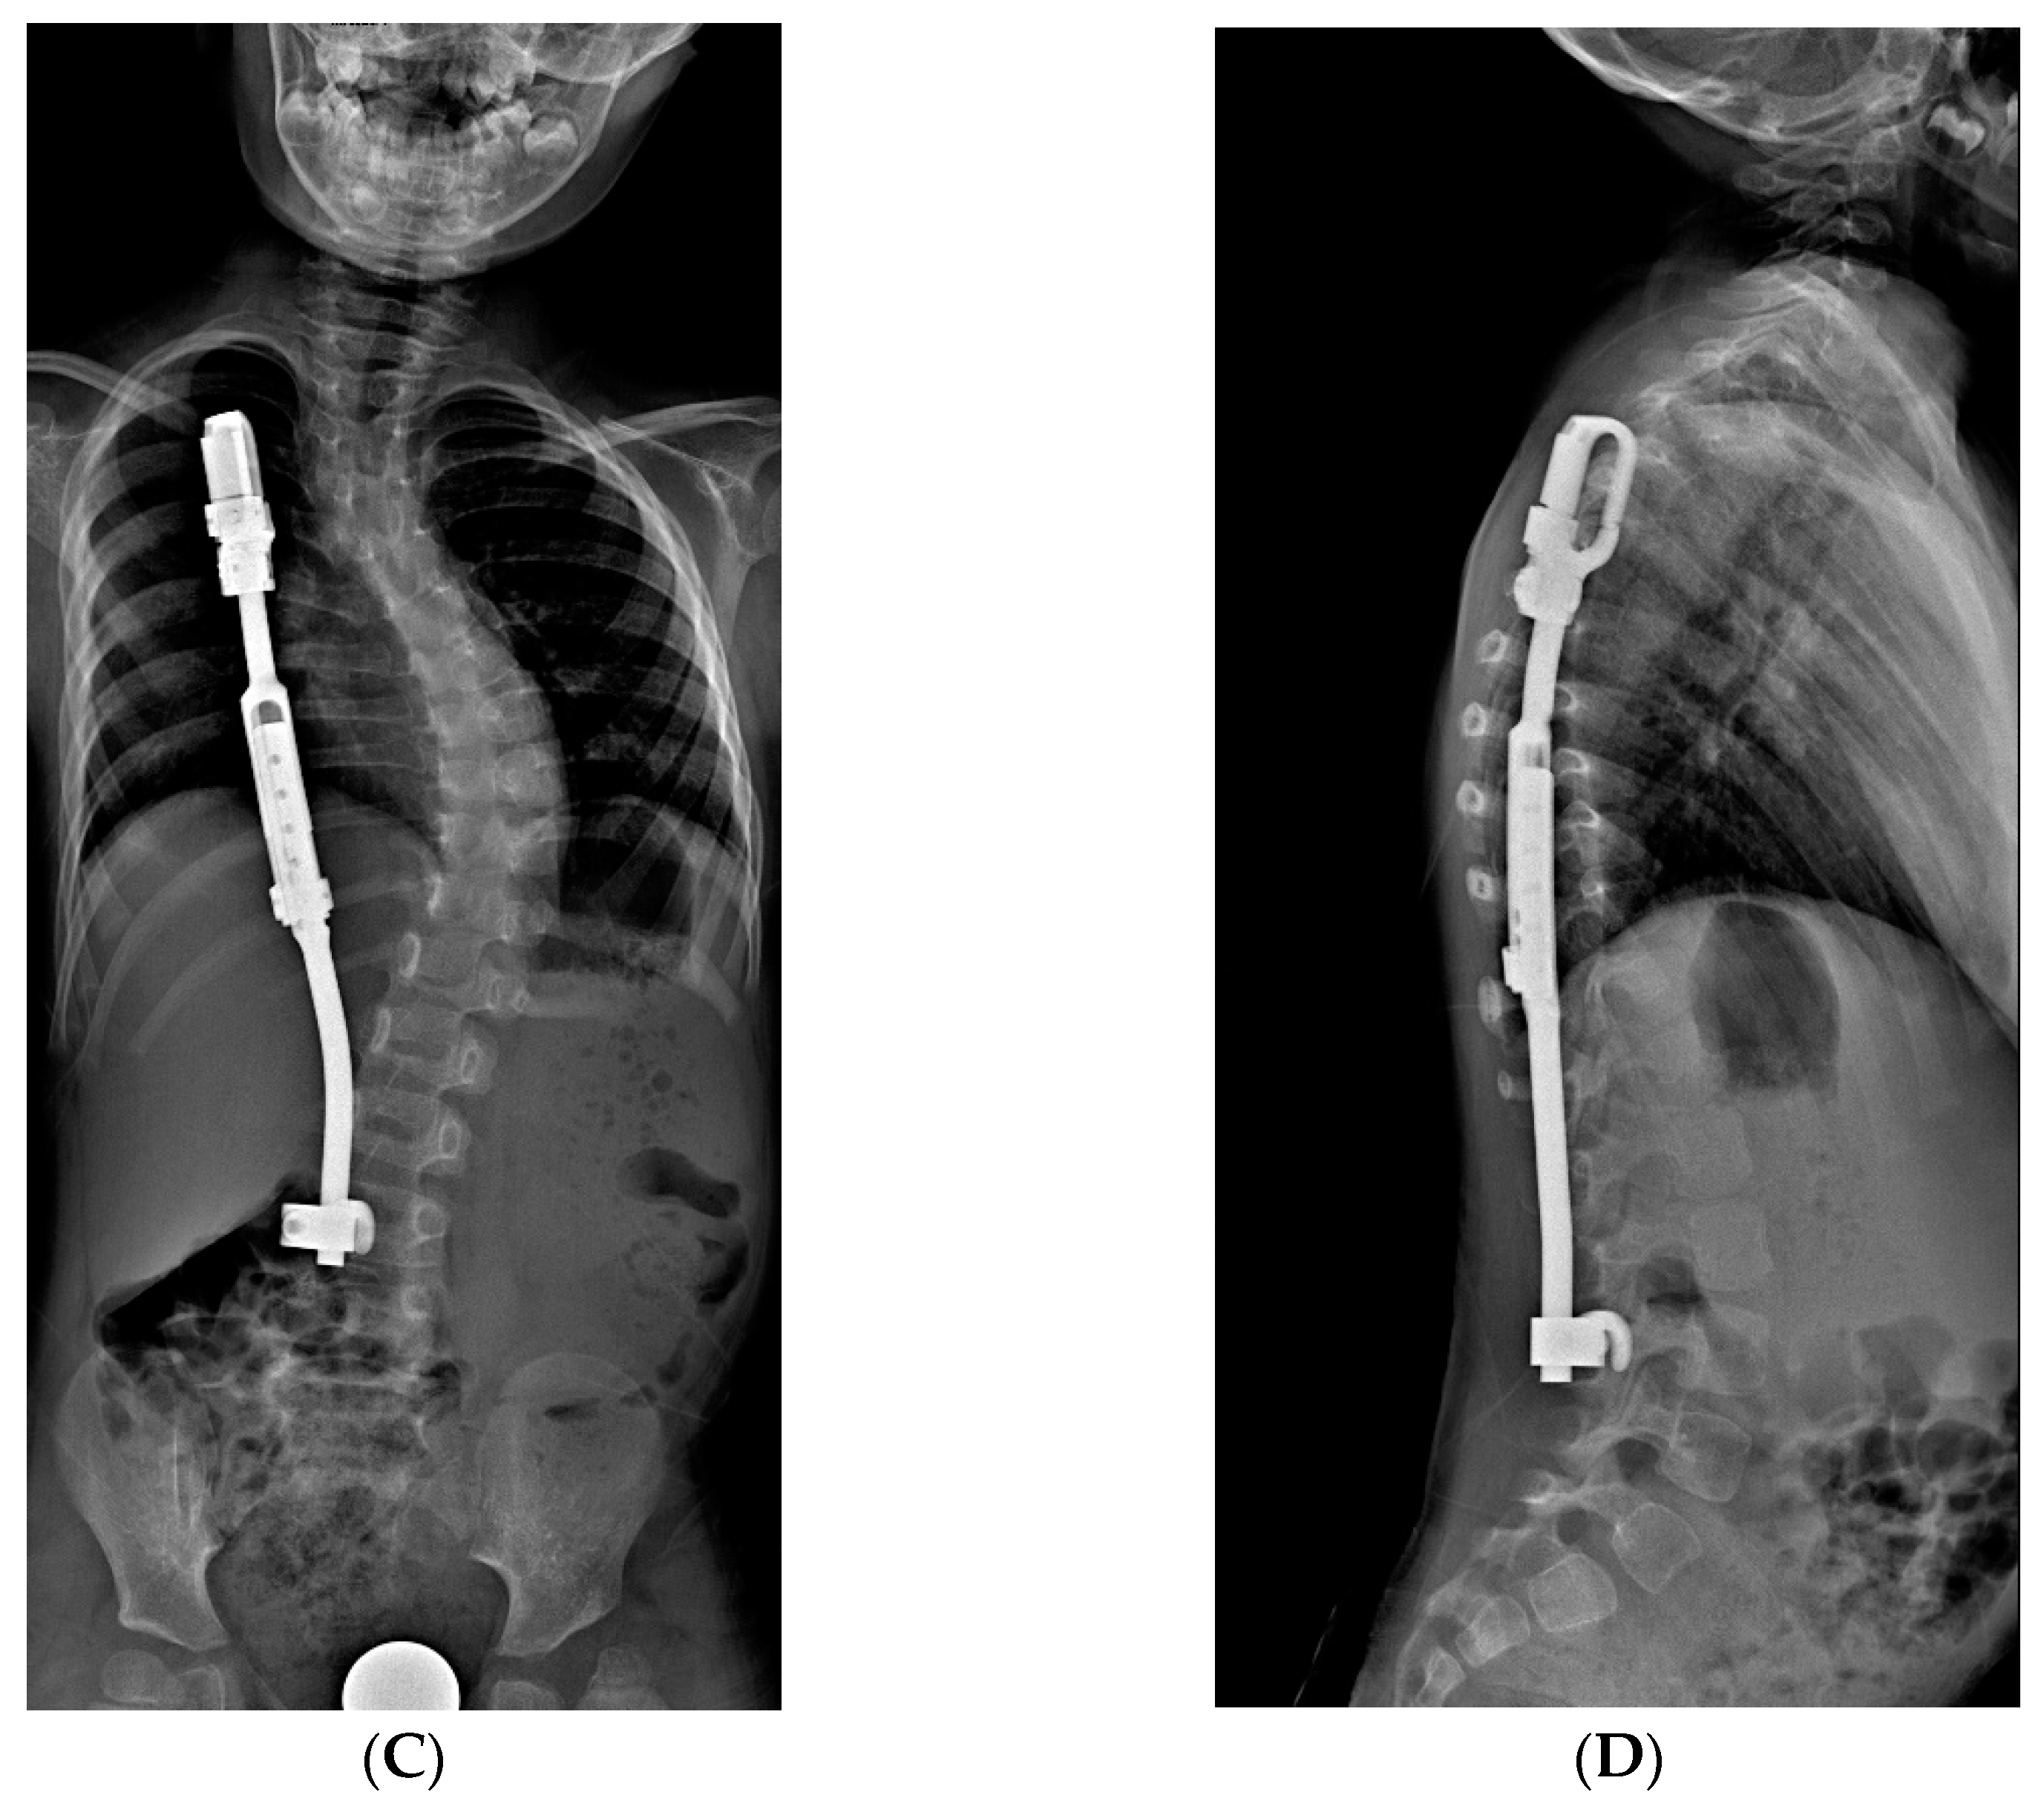

Figure 4.

X-Rays of early onset scoliosis (EOS) corrected with magnetically controlled growing rods (MCGR): (A) pre-operative antero-posterior X-ray view; (B) post-operative antero-posterior X-ray view; (C) pre-operative lateral X-ray view; (D) post-operative lateral X-ray view.